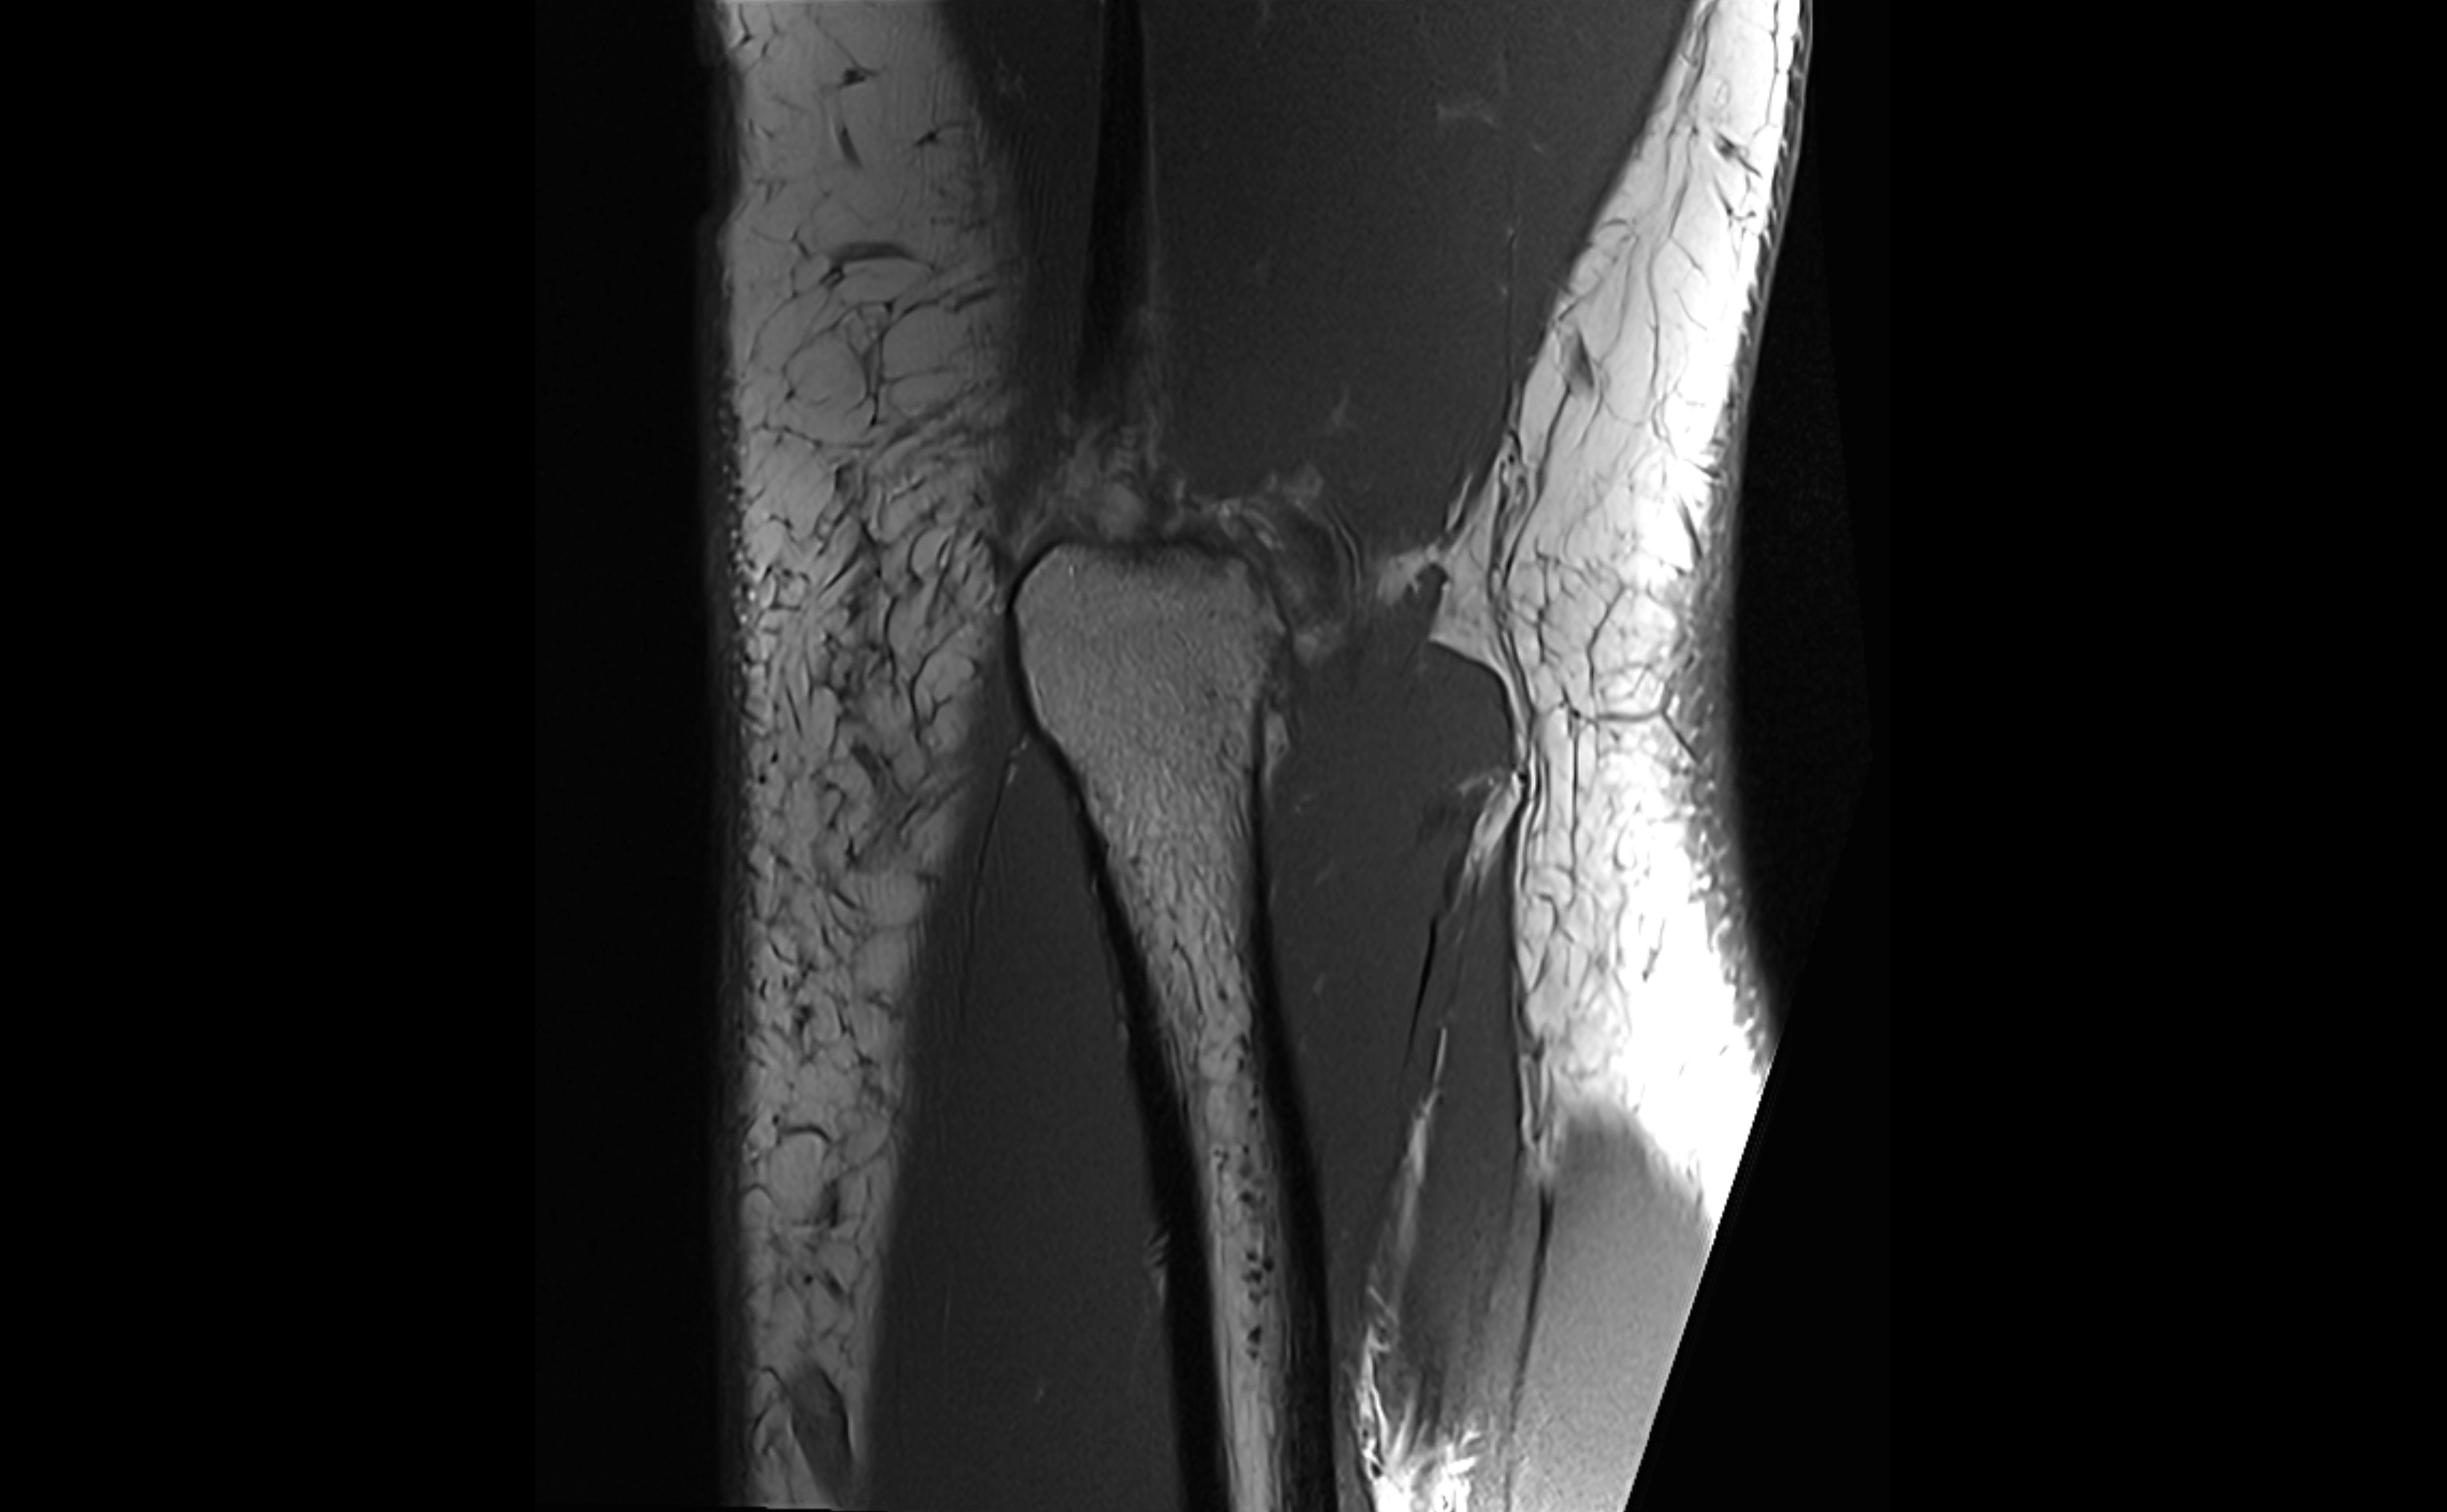

MRI images

image